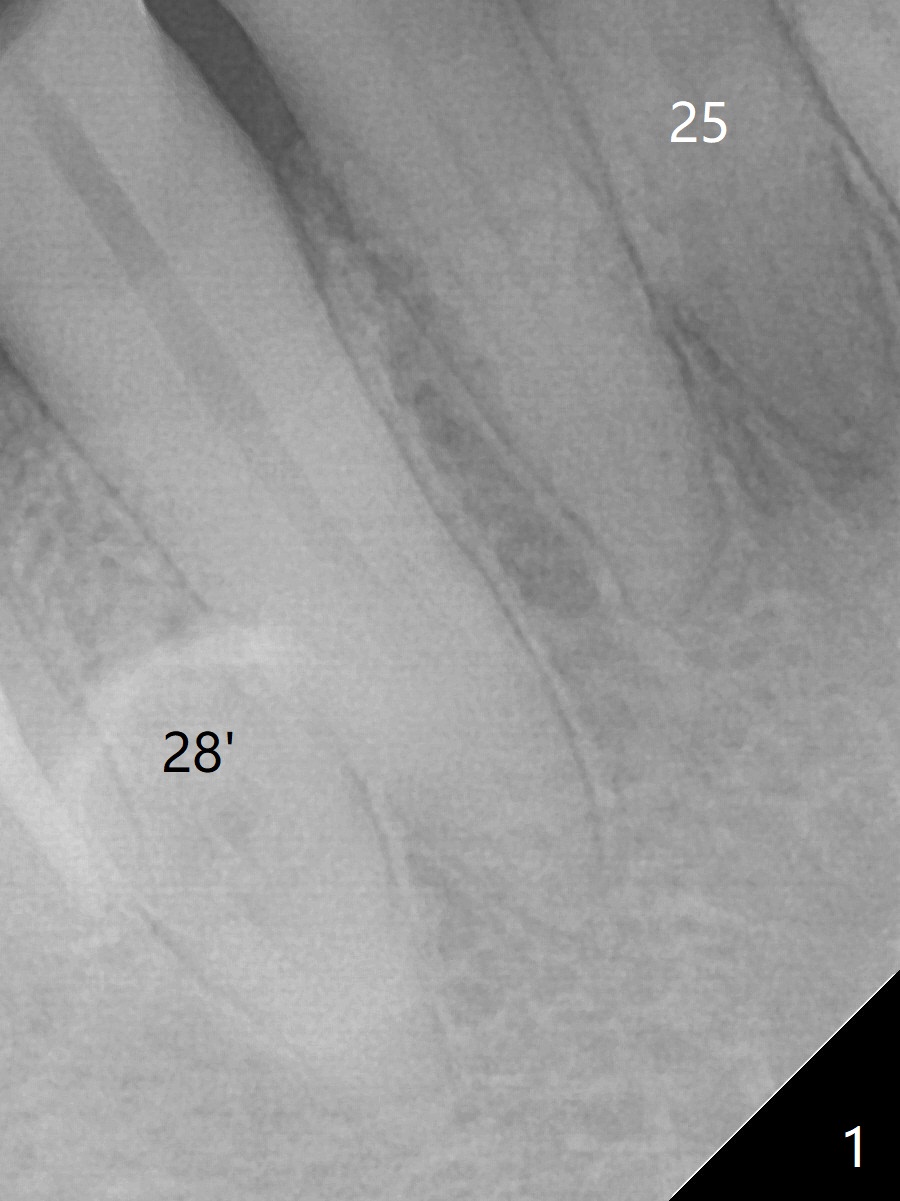

A 64-year-old man has multiple restoration and loves to eat crab. The lower incisors have severe wear. The tooth #25 is discolored with pulpal exposure and periapical radiolucency (Fig.1, 2 *). After insertion of 30/.04 master cone (Fig.3 (1 year 3 months post diagnosis)), RCT is finished with BioRoot RCS (bioceramic) and single GP (Fig.4). Nearly 10 months later, the patient returns with sinus track associated with the tooth #24 with PARL (Fig.5 *).